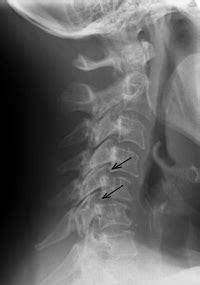

Diagnosis: How Doctors Pinpoint Cervical Facet Disease

Figuring out if you’ve got cervical facet disease involves a few key steps. First off, your doctor will likely start with a thorough medical history and physical examination . They’ll ask you about your symptoms, when they started, what makes them better or worse, and any past injuries you might have had. They’ll then physically check your neck’s range of motion, look for tenderness, and assess your posture. To get a clearer picture of what’s going on inside, imaging tests are usually the next step. X-rays can show bone spurs, joint narrowing, and other signs of arthritis in the facet joints. However, X-rays primarily show bone, so they might not reveal all the details of soft tissue damage. MRI (Magnetic Resonance Imaging) is often more helpful because it provides detailed images of soft tissues like cartilage, ligaments, and discs. It can show inflammation and degeneration more clearly. Sometimes, doctors might use CT (Computed Tomography) scans , which offer more detailed bone images than X-rays and can be useful for assessing bone structures. A really definitive way to diagnose facet joint pain is through diagnostic facet joint injections . In this procedure, a local anesthetic is injected directly into the suspected facet joint. If your pain is significantly reduced or completely relieved after the injection, it strongly suggests that the facet joint is the source of your problem. This diagnostic step is super important because it helps rule out other potential causes of neck pain and confirms the diagnosis before moving on to treatment.